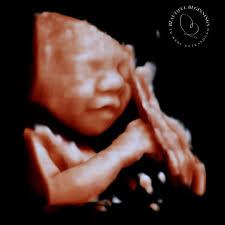

A 2D ultrasound shows a black and white image of your child, whereas 3D and 5D ultrasounds show more detail. Multiple 2D images are taken from various angles during the 3D ultrasound, and these are rendered together to create a 3D image of your baby. This scan can provide a clear image of the fetus, including the precise shape of the mouth, nose, cheeks, and eyes. In the form of a short video, 4D ultrasounds demonstrate movement.

As a result, you may notice your current baby yawning, sucking his thumb, making cute faces, or opening and closing his or her eyes. A 5D ultrasound centre in Dehradun has more technologically advanced ultrasound than a standard HD ultrasound. There is a virtual light source that acts as a digital flashlight, casting shadows and reflecting light to create a more defined 5D image. It also automatically reduces speckle, which improves image clarity significantly.